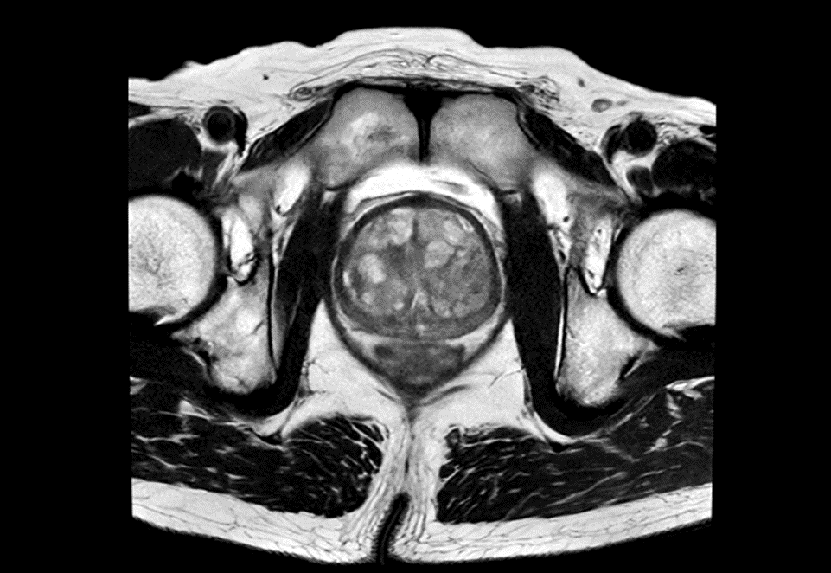

骨盤領域での臨床応用 ~PI-RADSに準拠した前立腺T2強調像~

前立腺マルチパラメトリックMRIの撮像条件や読影方法の標準化を目的として、Prostate Imaging and Reporting and Data System (以下PI-RADS) が提唱されている。PI-RADSが求めているT2強調像の分解能は、面内0.4×0.7mm以下、スライス厚3.0mm以下という高分解能が要求されるため、1.5T装置では十分なSNRを担保することが難しく、検査時間の都合上、それに準拠したシーケンスを組むことは容易ではなかった。しかし、AIR™ Recon DLにより空間分解能とSNRの向上の両立に加え、撮像時間の短縮が可能となるため、当院でもPI-RADS推奨条件下での検査を行うことができようになった(図7)。読影レポートにもPI-RADSカテゴリーが記載されるようになり、基幹病院への不要な紹介が減ることで患者の身体的・精神的な負担を軽減できるだけでなく、医師にも有益な情報を提供できている。

図7 PI-RADSに準拠した前立腺T2強調像

空間分解能:0.4×0.7×3mm 撮像時間:2:24min